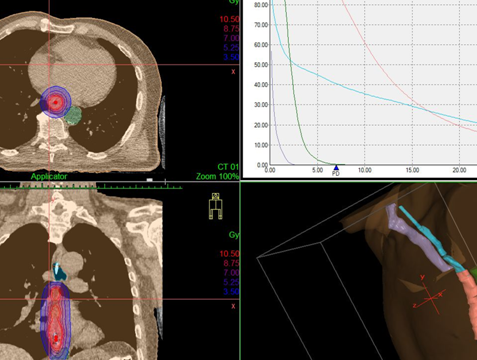

Разновидности лучевого лечения:

• Наружное (дистанционное). Источник ионизирующего излучения находится на расстоянии от пациента.

• Контактное (называется «брахитерапия»). Источник излучения эндоскопическим методом размещается как можно ближе к новообразованию. Ионизирующие лучи проходят малое расстояние, поэтому достигают опухоли, но мало затрагивают расположенные рядом ткани. Лечение позволяет уменьшить новообразование и восстановить проходимость.

image016.png Дозное распределение, получаемое при дистанционной конформной лучевой терапии и внутрипросветной брахитерапии